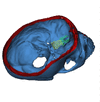

since i suspect you are not familiar with cephalometric landmarks, i will add some pics to better illustrate what is meant with increased SNA and SNB

6948e52f08233377927ef47a8b40b48ce12d1f95.jpg

6ff5f7486c61b4ee7bab946c78a8aeee0e2ecea2.jpg

mean SNAr seems to be around 120-125 degrees looking at a bunch of studies, SD around 5-6 degrees